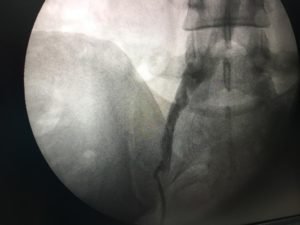

- IVC filter insertion